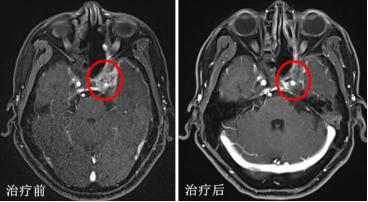

▲典型病例:局部晚期复发鼻咽癌患者,病灶侵袭海绵窦、包绕神经血管,治疗难度大。接受重离子治疗后,病灶完全退缩。

根据最新研究成果,采用单纯重离子治疗光子调强放疗后复发的206例鼻咽癌,患者两年总生存率达83.7%,且其中大多数(139例,67%)为治疗难度更大的局部晚期患者。与之相比,复发鼻咽癌再程光子放疗后患者两年总生存率仅为60%左右,局部晚期患者的两年总生存率更是只有40-50%。同时,再程放疗最常见的并发症——鼻咽黏膜坏死发生率仅为16%,也远低于光子调强放疗的40%。“这是目前肿瘤粒子放疗领域唯一一项公开发表的关于重离子放射治疗复发鼻咽癌的研究成果。我们累计治疗复发鼻咽癌近400例,积累了丰富、成熟的治疗经验,疗效也达到世界先进水平。”医院头颈及中枢神经肿瘤科主任孔琳说。